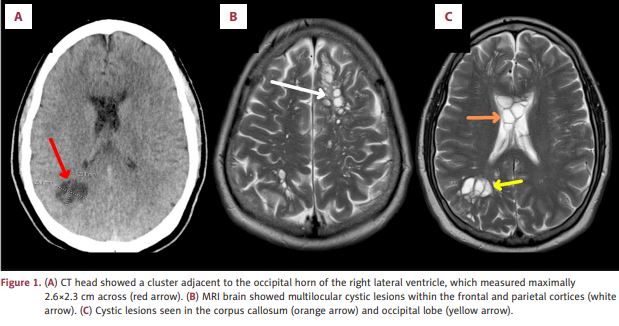

The scans revealed numerous cysts nestled within his brain. After more tests, the doctors found the root cause of his condition: parasitic tapeworm larvae, known to cause neurocysticercosis, a rare and dangerous infection of the brain.

Neurocysticercosis is a condition caused by parasitic tapeworms when cysts embed within the nervous system, according to the study. These parasites may be located anywhere from brain parenchyma to the ventricular system and spinal cord. American Journal of Case Reports